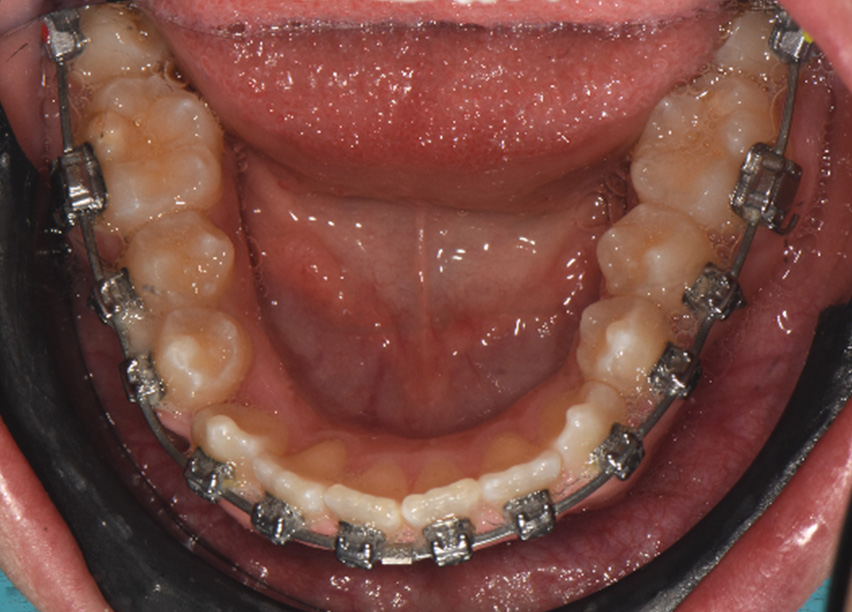

Observations: At the end of phase 1, most of the rotations had been corrected and arch development was progressing well. The crowding had been resolved and spaces were visible due to arch development with the first rectangular wire. Additionally, primary torque control was observed. The time frame of these changes was six months.

During this phase, the wires were changed to 0.018 x 0.0275 CuNiTi Ultima U/L. Tie-back elastic used between 6s and crimpable hooks to avoid space opening and the elastics were changed to night-time vertical frontal elastics to help with the eruption of the maxillary incisors. For this, the anterior bite turbos were removed and the disarticulation was moved to the posterior area, on U7s. A few brackets were repositioned after panoramic x-ray control.

Observations: Arch form was really improved in both shape and width. The variable torques allowed the Ultima wires to express the deflection and the torque changes were very close to the final goals. The time frame was 3 months.